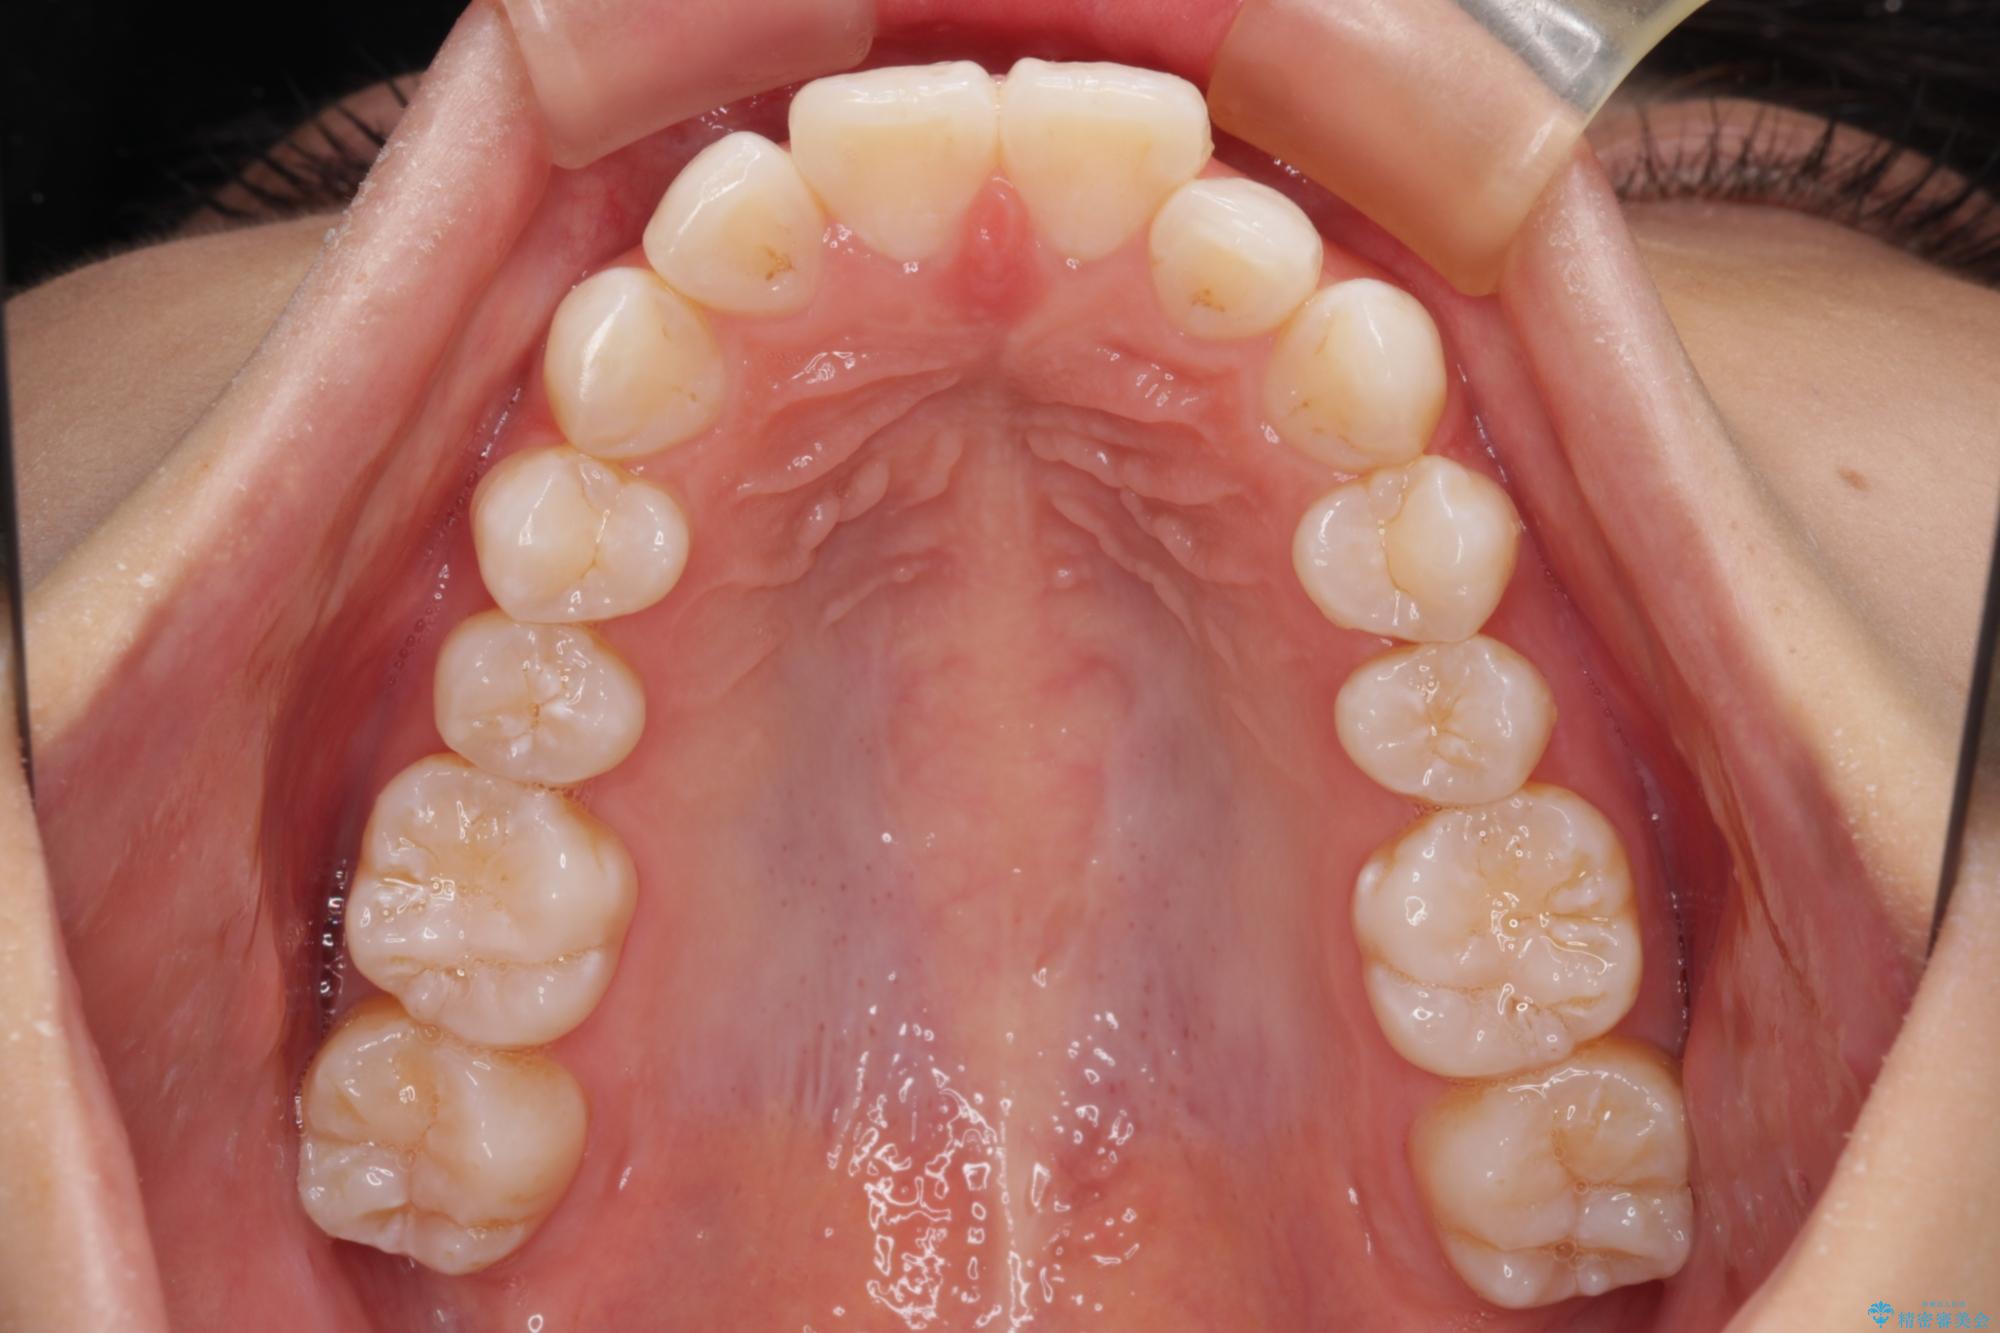

- 口を閉じたときに飛び出してしまう上顎前歯を気にして来院された患者様です。

下顎はデコボコが気になっていたため、上下左右第一小臼歯4本を抜去して、ワイヤー装置にて口元の突出感を改善するよう矯正治療を行うこととしました。

下唇に前歯が当たって跡が残ってしまう状態でしたが、スッキリとした口元に仕上げることができました。